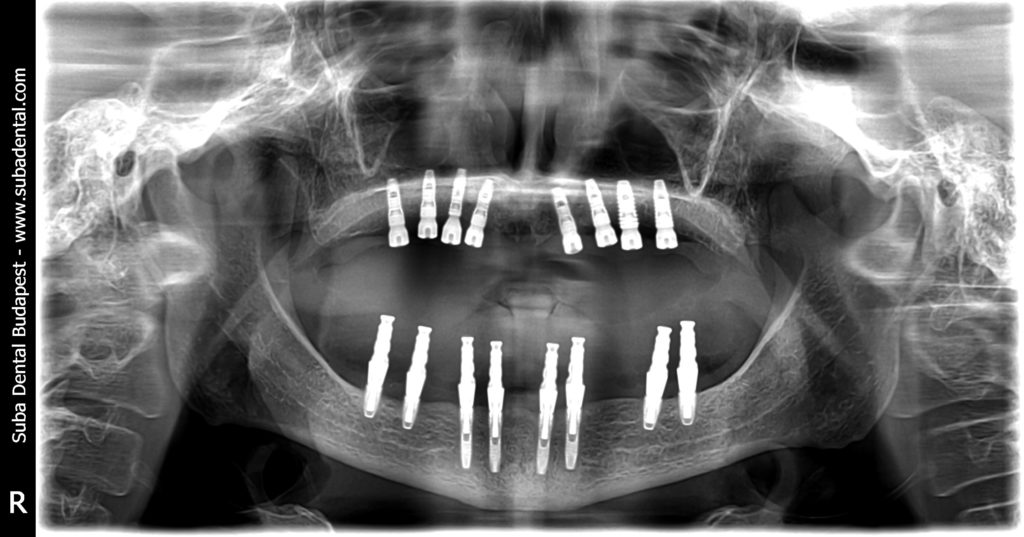

Radio panoramique de contrôle après la pose de 16 implants (la stabilité des implants est bonne alors les vis de cicatrisation – healing abutment - ont été posées)